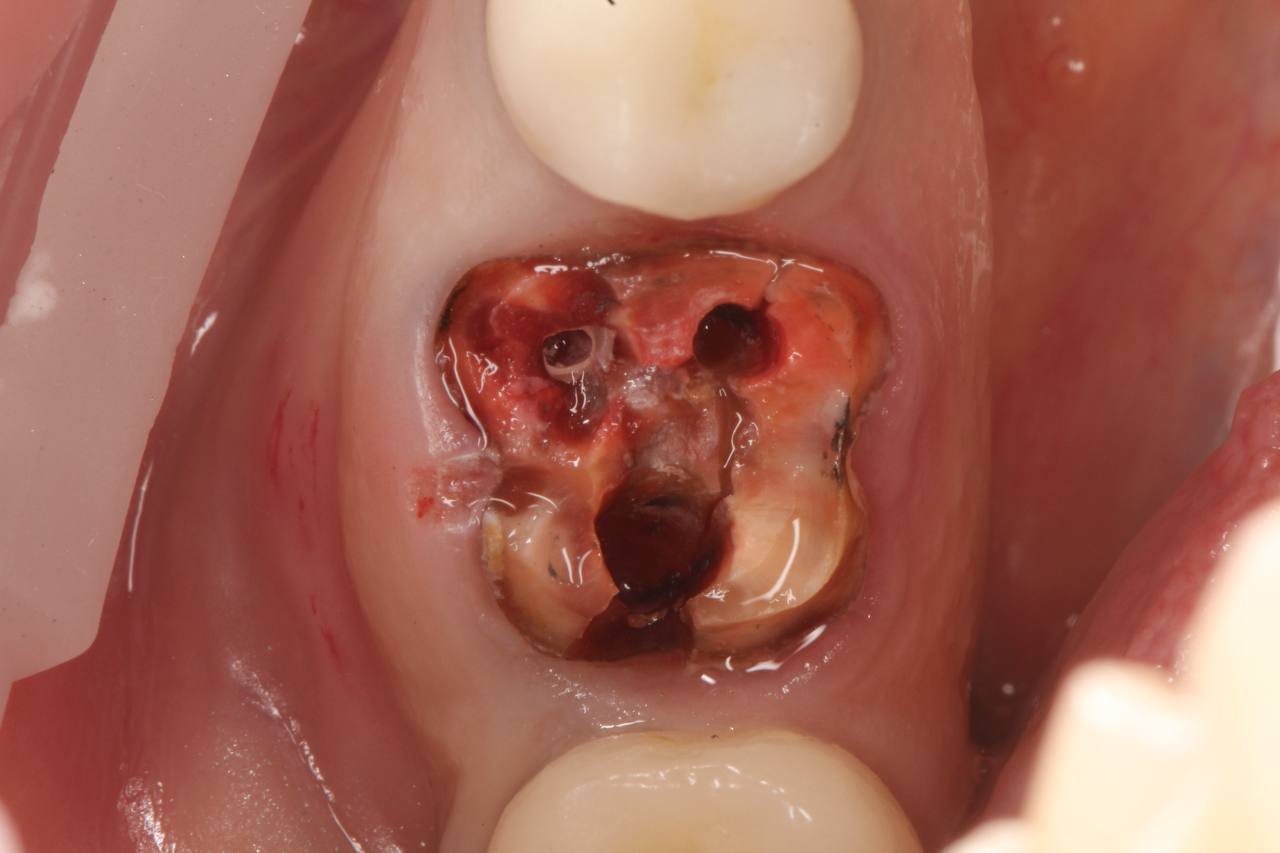

• Аккуратное удаление